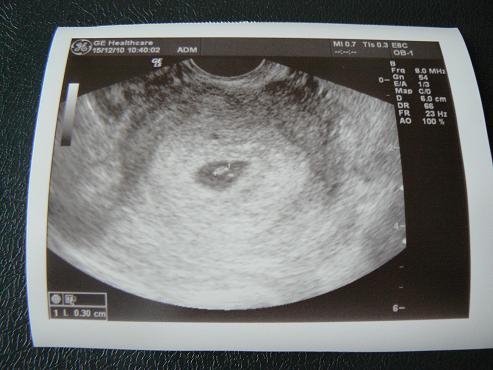

Szóval minden rendben volt,15 mm-es petezsákban 3 mm-es babóca csücsült!!!! :D

Ja,és hát a lényeg: PULZÁLT A SZIVECSKÉJE!!!!!!! :D :D :D :D :D

kaptunk képet is:

nagyobbat nem enged ez a vacak felrakni,de azért ezen is látszik a lényeg!

A babó a 2db x között van,és az x-ek között kb. félúton pulzált,ahol az a pici sötét pötty van :D

No,itt már jobban látszik az x :D

szóval a 2 x között a világos paca a baba,és rajta a sötét folt pulzál :D